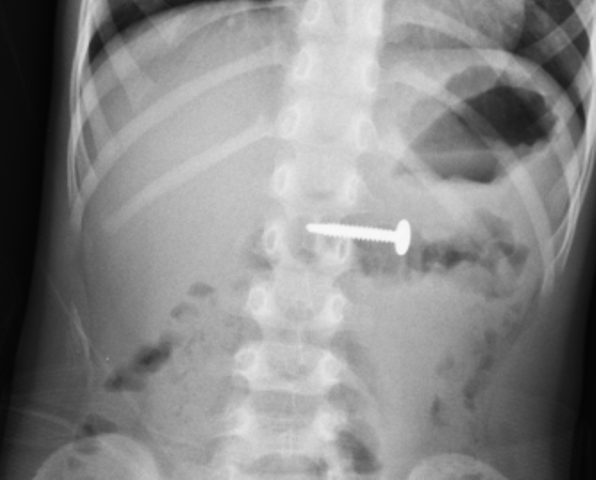

Báo Sức khỏe & Đời sống cho biết, theo lời kể gia đình, cách vào viện 5 giờ bệnh nhân tự nuốt vật lạ là một đinh vít. Sau khi nuốt gia đình đưa đi khám tại Trung tâm y tế TP Móng Cái chẩn đoán dị vật đường tiêu hóa. Bệnh nhân được đã được hội chẩn và chuyển tới Bệnh viện Sản Nhi Quảng Ninh. Kết quả chụp X-quang cho thấy hình ảnh dị vật nằm ở vị trí tá tràng, kích thước khoảng 3cm.

Hình ảnh phim chụp Xquang thấy rõ dị vật - Ảnh: BVCC. |